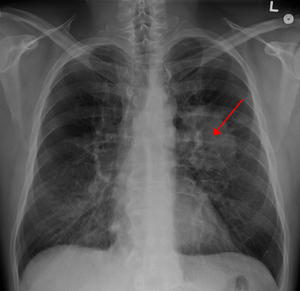

• 有哪些主要的肺癌症状

有哪些主要的肺癌症状

在肺癌患者中,最主要的 肺癌症状 就是咳嗽,刊登在《美国胸科杂志》上的一项研究发现,约60%的肺癌患者在正式确诊时有慢性咳嗽症状。但是普通感冒、咽喉炎也会咳嗽,这就导致了很多肺癌患者在早期咳嗽时并没有引起重视,没有及时就医进行检查,最终错过 ...

• 常见的肺癌早期症状

常见的肺癌早期症状

在肺癌病人中,咳嗽、咯血咳嗽是最常见的 肺癌早期症状 。咯血则最有诊断意义,多为痰中带血丝。凡呼吸道症状超过两周经治不愈,尤其是痰带血、干咳或老年慢性支气管炎病人,近期咳嗽声音或性质改变,要高度警惕肺癌的可能。由于咯血的量少或间歇出现, ...

• 哪些是肺癌早期症状

哪些是肺癌早期症状

肺癌,它高居全球癌症首位,很多病人认为肺癌一定会有咳嗽、咳痰和痰中带血的表现,其实这样的观点并不正确。 肺癌早期症状 不明显,容易被误诊、漏诊,只有当肿瘤比较大,对周围组织的侵犯较多或出现远隔脏器转移时,才会有较为明显的症状。而肺癌所致 ...